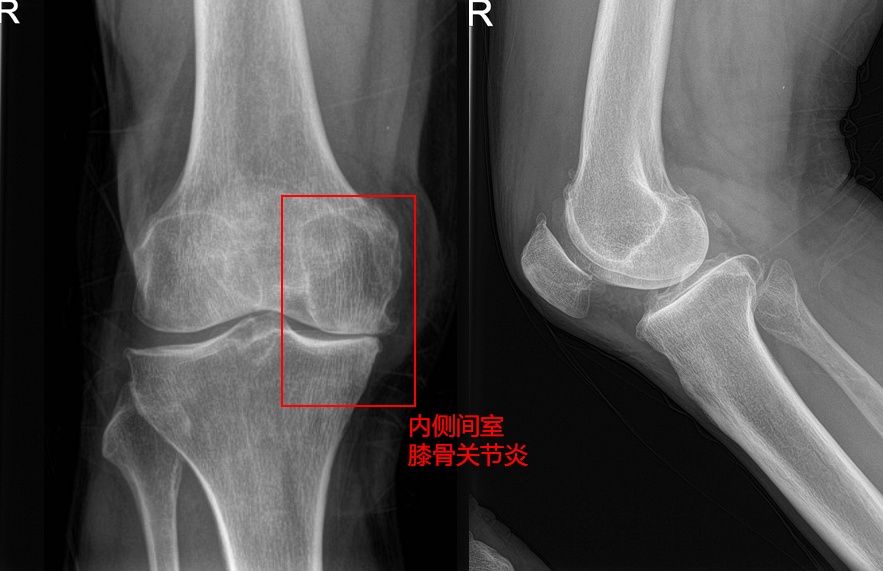

包老先生时年71岁,已被右膝关节的骨关节炎折磨许久,在当地医院尝试过口服止痛药物、封闭、针灸等保守治疗。近3月来感觉右膝关节疼痛比之以往明显加重,膝关节伸直受限,下蹲后难以直接站立,上下楼梯及行走时困难。结合病史、x线、核磁共振辅助,检查结果确诊为“右膝关节退行性病变”。包老先生来到同济大学附属同济医院就诊后,同济大学附属同济医院运动医学科程飚主任考虑到患者的膝关节病变主要集中在内侧间室,结合患者的诉求,决定为包老先生行右膝单髁关节置换手术,解决他的病痛。

在人类直立行走后,身体重心位于身体中央,在膝关节上产生内收力矩,胫骨平台和股骨远端内侧部分就成为了承载体重最主要的负重区。因此这部分负重区也是最容易磨损,导致半月板的慢性损伤和软骨磨损,甚至膝关节内翻畸形。所以许多患者的膝关节炎先发生在内侧,再逐渐导致外侧和髌股关节的退变。